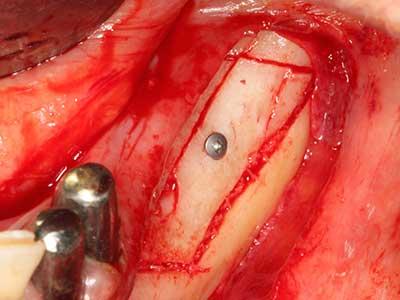

Abb. 17a: CT-Aufnahme eines wachstumsprogredienten Osteoms in unmittelbarer ...

Abb. 17b: Lagebeziehung zum Alveolarkanal mit Nervirritation (laterale und koronare Ansicht).

Abb. 18: Präparation eines Kortikalis-Deckels mit der Piezo-Knochensäge (Piezomed, W&H).

Abb. 19: Operationssitus nach Neurolyse und Osteomentfernung.

Abb. 20: Der entnommene Knochendeckel wird readaptiert und durch eine Osteosyntheseschraube (KLS Martin, Tuttlingen) fixiert.

Sollen chirurgische Eingriffe mit unmittelbarer Knochenbeziehung an empfindlichen Strukturen wie Blutgefäßen oder Nerven erfolgen, so bergen rotierende Instrumente ein erhebliches Potential an iatrogener Schädigung. Gerade bei Nervdarstellungen nach iatrogener Schädigung, oder aber im Zuge einer Nervlateralisation für resektive und rekonstruktive Eingriffe oder Implantatinsertionen können piezoelektronische Geräte hilfreich sein Knochendeckel zu präparieren und nervnahe Hartgewebsanteile zu entfernen (Abb. 17-20). Ein leichter Kontakt des Nervstrangs zur Piezospitze bleibt dabei in der Regel folgenlos – allerdings kann eine unvorsichtige Vorgehensweise mit sägeartigen Bewegungen bzw. Ansätzen bei noch vorhandener knöcherner Unterlage durchaus temporäre oder aber auch permanente Nervschädigungen verursachen. Das Risiko einer solchen Schädigung wird jedoch als wesentliche geringer eingeschätzt als unter Anwendung von Säge- oder Fräsinstrumenten (Pereira, Gealh et al. 2014).